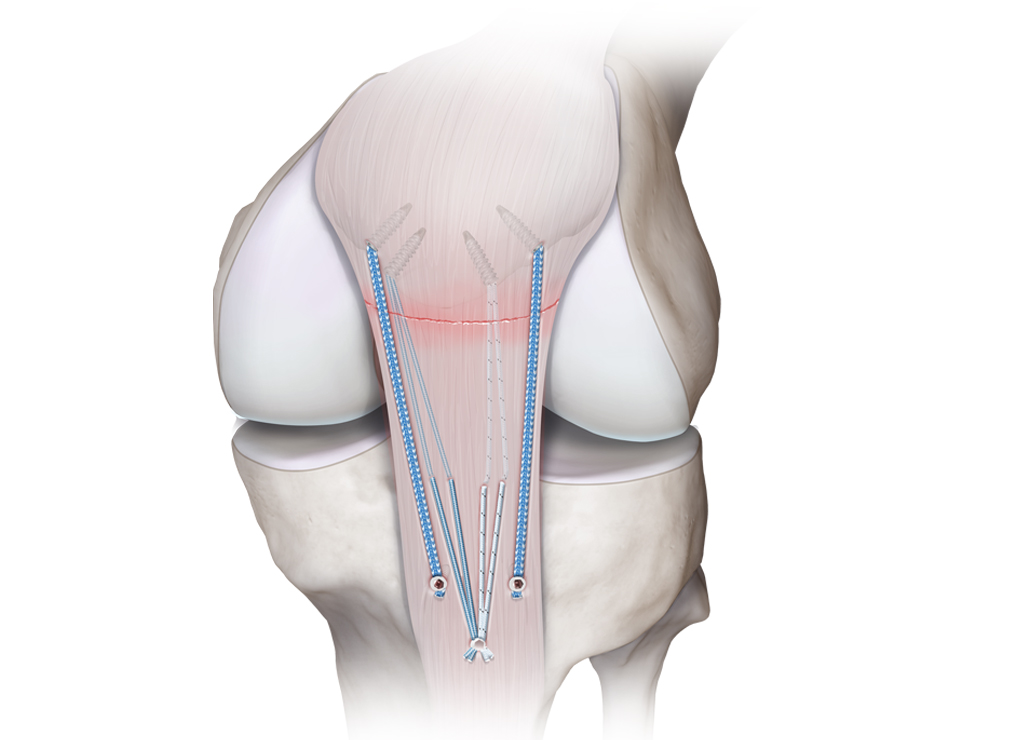

Nos casos em que as medidas conservadoras não proporcionam alívio adequado da dor ou quando há rotura completa do tendão, pode ser necessária uma intervenção cirúrgica. A cirurgia tendinosa pode envolver a reparação do tendão danificado, a remoção de tecido degenerado ou a reconstrução do tendão utilizando enxertos ou técnicas de reforço.

As roturas do tendão quadricipital e do tendão rotuliano ocorrem geralmente devido a traumatismos diretos, lesões de sobrecarga com enfraquecimento progressivo do tendão (tendinopatia), movimentos de aceleração/desaceleração com contração súbita do músculo contra resistência, resultando numa tensão excessiva no tendão. Habitualmente existe uma dor intensa e súbita na parte frontal do joelho, inchaço e incapacidade para estender o joelho ou manter a perna esticada. O tratamento pode variar conforme a gravidade da lesão. A estratégia não operatória com repouso, gelo, compressão e elevação, seguido de fisioterapia. Na maioria das situações de rotura completa, a cirurgia é necessária para reparar o tendão.